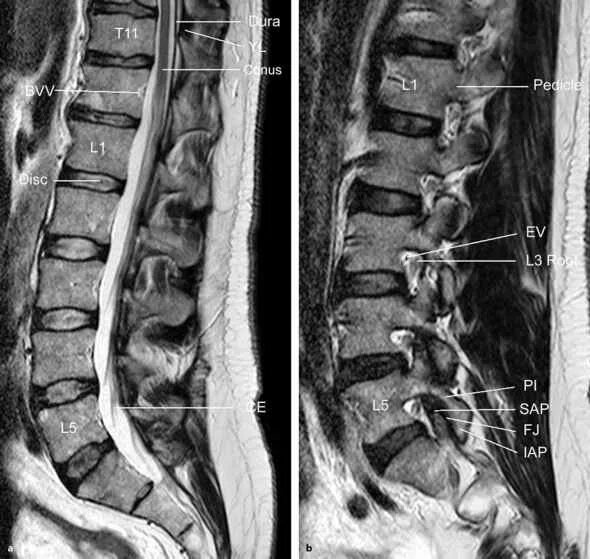

Перед мрт позвоночника можно кушать